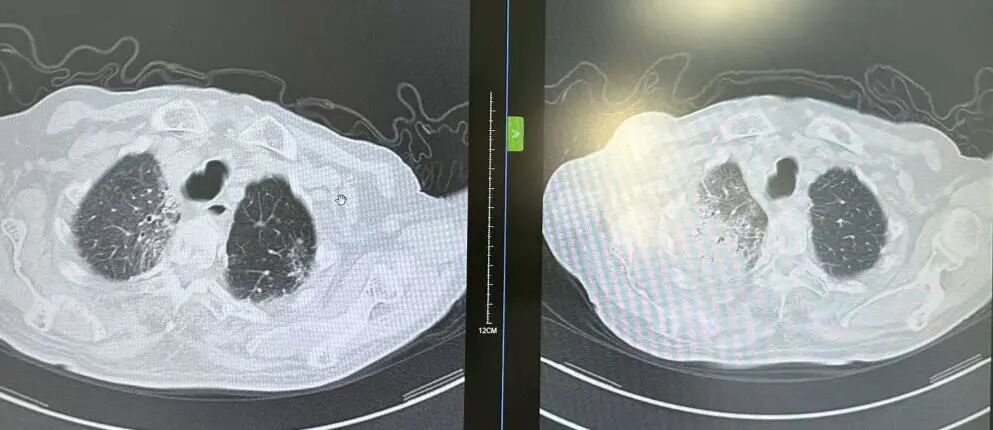

内容提要 近日,市第二人民医院呼吸与危重症医学科宋刚主任团队,成功救治一名98岁高龄、患有罕见隐源性机化性肺炎(COP)的患者。面对高龄、病情复杂、诊治风险高等重重困难,团队凭借精湛医术与丰富经验,帮助老人转危为安,再次彰显了科室在危重症救治领域的强大实力。 挑战一:高龄禁区,敢为人先 患者因发热、咳嗽,伴乏力、气短、喘息等症状来院,此前在当地诊所使用多种抗生素均无效,病因成谜。要明确诊断,支气管镜检查是关键一步,但对近百岁老人而言,此项操作犹如踏入“生命禁区”,风险极高。宋刚主任团队没有退缩,在全面评估、周密预案、充分沟通的基础上,凭借丰富经验成功实施检查,为后续治疗打开了至关重要的突破口。 治疗前患者肺部CT影像 挑战二:罕见病症,迷雾重重 检查结果指向一种罕见疾病——隐源性机化性肺炎(COP)。此病本就少见,好发于50~60岁人群,在近百岁老人中发生更是极为罕见。更为棘手的是,患者还伴有胸腔积液。COP通常表现为发热和肺部影像上的“游走性”阴影,很少合并胸腔积液,这使得诊断工作如雾里看花,难度倍增。 挑战三:病菌分辨,生死抉择 诊断刚明,新的考验接踵而至:患者标本中检出了根毛霉菌。COP的核心治疗是糖皮质激素,若根毛霉菌是致病菌,激素可能引发真菌扩散,用药无疑将导致致命风险。因此,辨别其是“定植菌”还是“致病菌”,成为治疗成败的关键。 宋刚主任团队凭借丰富的临床经验和严谨的诊疗思维,结合患者肺部影像特征、症状及化验结果,综合判断认为该霉菌属于定植菌,从而排除了治疗障碍,确保了后续用药安全。 精心施治,百岁老人转危为安 在后续治疗中,团队如履薄冰,精细平衡抗凝与激素治疗带来的出血、感染等风险,制定个体化方案。经过精心治疗与护理,老人肺部病灶显著吸收,各项指标恢复正常,最终康复出院。 治疗前后肺部CT影像对比,左侧为治疗后,右侧为治疗前。 此次成功救治,充分体现了市二院呼吸与危重症医学科在复杂疑难呼吸道疾病及危重症领域的综合救治能力。面对高龄高风险患者,团队始终以患者为中心,在风险与疗效间精准把握,用技术与责任守护每一位患者的呼吸健康。 人民医院 人民名医 宋刚 主任医师 ·葫芦岛市第二人民医院呼吸与危重症医学科主任 ·辽宁省生命科学学会东北呼吸与危重症医学(PCCM)分会辽宁省基层委员会副主任委员 ·辽宁省细胞生物学学会放射粒子治疗专业委员会理事 ·辽宁省抗击新冠肺炎疫情先进个人 ·辽宁省预防医学会第一届吸烟相关疾病防治专业委员会委员 ·葫芦岛市劳动鉴定委员会专家库成员 ·葫芦岛市医学会呼吸内科学分会第三届委员会副主任委员 专业特色:擅长呼吸系统疑难及急危重患者的救治,如急慢性支气管炎、支气管哮喘、慢性阻塞性肺疾病、肺炎、肺栓塞、肺癌、间质性肺疾病、睡眠呼吸暂停综合征等,尤其擅长有创无创机械通气、支气管镜下相关检查及治疗(TBNA、气道支架置入术、球囊扩张等)、全肺灌洗术等领先技术,发表国家级期刊多篇。 出诊时间:每周二、周四全天 出诊地点:门诊二楼东侧35诊室